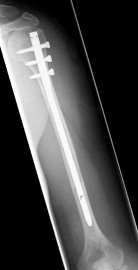

Oberarmschaftbruch1Oberarmschaftbruch2

Picture: Here you can see a completely shifted upper arm fracture with a strong bend of the axis. First the operative treatment was performed by repositioning the bone and internal splinting of the fracture with a medullary nail.